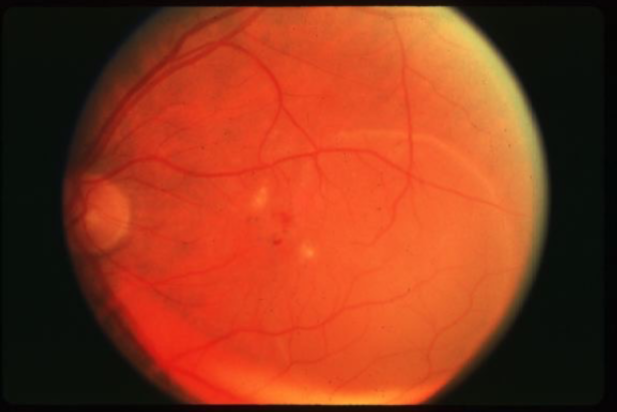

drusen

drusen

hard drusen

soft drusen

soft drusen

soft drusen

soft drusen